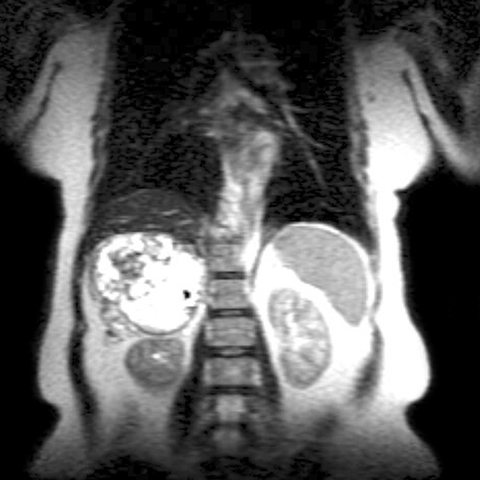

42-year-old-male presents with episodic headache, diaphoresis, and tachycardia. [1 of 3]